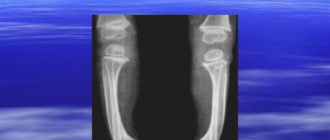

Варус и вальгус стопы

Варусная деформация стопы: причины, виды положения и лечение К числу распространенных ортопедических патологий относится